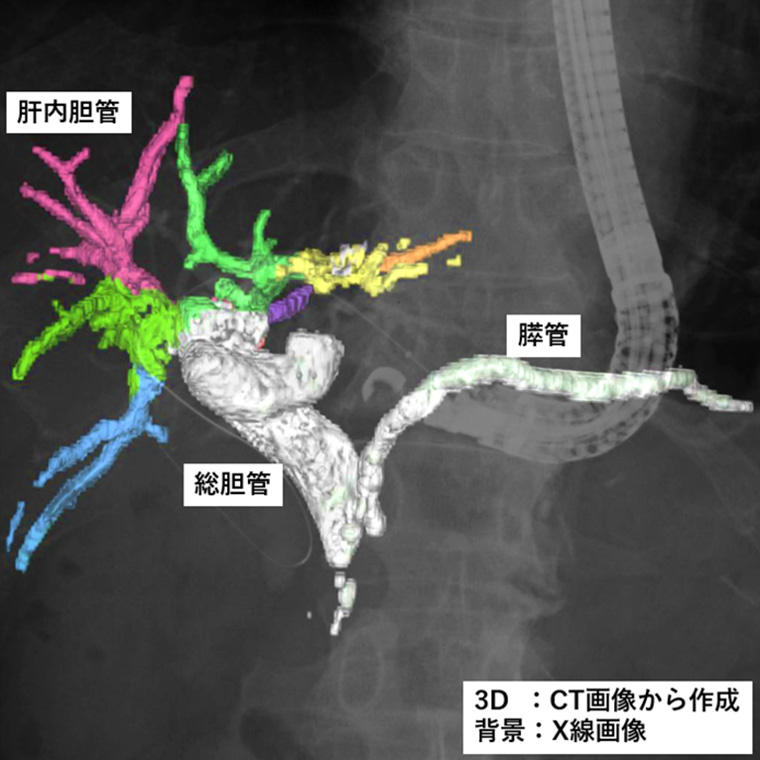

また、今回発売する二つのモデルは、2025年4月に発売したソフトウェア「VisualAID-ERCPプランニング-」*7にも対応。本ソフトウェアは、ERCP中にCUREVISTAシリーズで撮影したX線透視画像上に3Dで作成した胆管・膵管の画像を重ねて表示することで、臓器との重なりなど解剖学的構造の把握が容易になることが期待できる。本ソフトウェアでは、これまでCT画像とMRCP画像*8で3D画像を作成する必要があったが、今回新たにCT画像のみで3D画像を作成できるようになった。これにより、MRI撮影を実施しない医療機関での対象被検者の増加が見込まれる。さらに3D画像作成時にCT画像とMRCP画像の位置合わせの作業が不要となることでワークフローの向上が期待できる。同社のIT技術とX線透視装置を連携させた新しいワークフローにより、医師の診療の高度化・効率化に貢献する。

「CUREVISTA Open ff」は、テーブルトップを一切スライドさせずに、X線管アームを縦方向と横方向に動かすことができる「2WAY ARM」を採用している。X線管アームに合わせて、テーブル内のFPD(Flat Panel Detector)も縦・横に動かせるため、内視鏡検査や経皮経肝胆嚢ドレナージ*10にて被検者を動かさずに透視や撮影の視野*11を移動できる。また「CUREVISTA Apex ff」は、縦方向と横方向に加えて斜め方向の移動が可能な「3WAY ARM」を採用。被検者を動かすことなく角度を変えて観察できるため、肝内胆管*12の重なりや奥行きを確認できる。